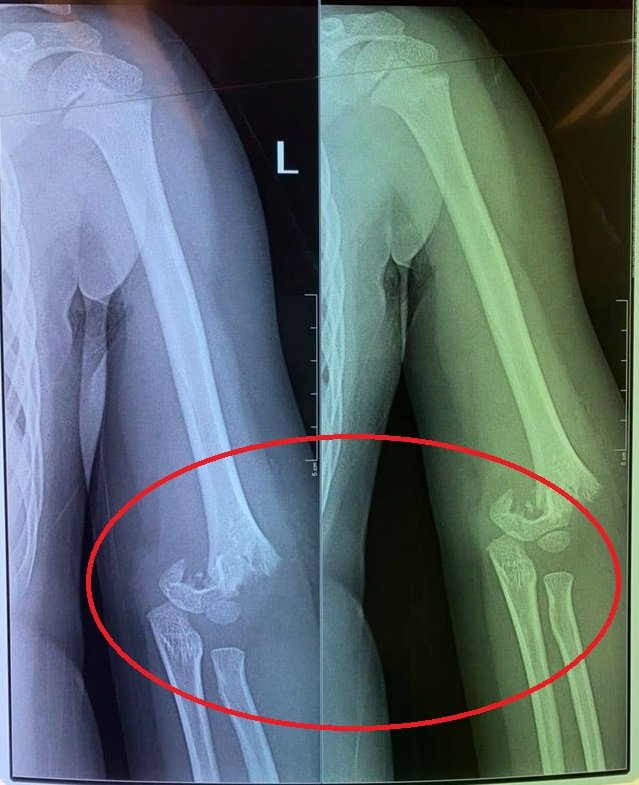

Con chị H. đã bị 1 bạn cùng lớp đẩy ngã từ cầu trượt văng ra ngoài làm gãy khuỷu tay. Tuy nhiên nhà trường lại không đưa bé T. đi bệnh viện luôn. "Tầm 12h trưa, tôi nhận được cuộc điện thoại của nhà trường báo: "Con nhà chị sáng đi học bị ngã, tay sưng và đang cho lên bệnh viên Bạch Mai". Sau đó tôi đi ra bệnh viện Bạch Mai thì cô hiệu trưởng báo bệnh viện Bạch Mai sẽ chuyển con lên bệnh viện Xanh Pôn. Tôi ngồi đợi con ở sảnh bệnh viện, đến khi cô hiệu trưởng đi ra thì thông báo: "Mẹ làm hồ sơ nhập viện để mổ cho con".

Con chị H. bị gãy phần khuỷu tay.

Chị H. cho biết, lúc nghe tin chị rụng rời tay chân, bàng hoàng không thốt nên lời. "Tôi đi vào phòng cấp cứu và được bác sĩ dặn phải thật bình tĩnh. Bác sĩ cho biết, may mà con tôi không bị liệt tay. Cháu bị gẫy tung khuỷu tay và phải được mổ ngay lập tức".